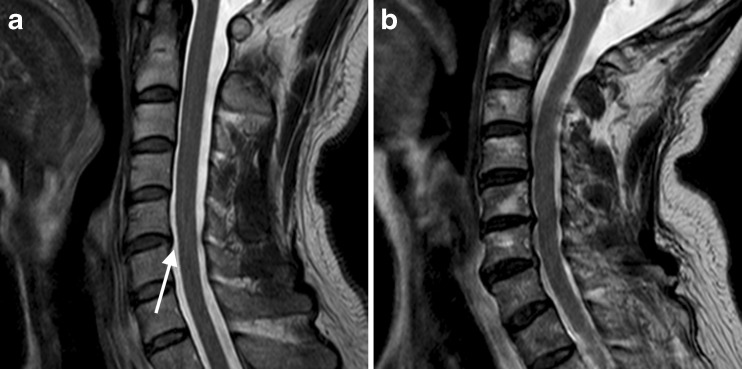

Fig. 2.

T2-weighted fast spin-echo images in the sagittal plane of one patient from group 1 (a) and one patient from group 2 (b). High intensity indicates cerebrospinal fluid between the cervical spinal cord and dura in a (arrow); this is absent in the compressed areas in b

By referring to T2-weighted images, two experienced neuroradiologists (M.H. and S.A.) classified the patients into two groups in consensus: (1) uncompressed spinal cords (residual cerebrospinal fluid (CSF) signal between the spinal column and spinal cord on the T2-weighted images); and (2) compressed spinal cords (cervical canal narrowing and no residual CSF signal between the spinal column and spinal cord at the level of narrowing on T2-weighted images) (Fig. 2). On the axial images of the calculated maps, a region of interest (ROI) was drawn manually on the spinal cord by an experienced neuroradiologist M.H.; the ROI included both white matter and grey matter, excluding any CSF contribution, at spinal canal levels C3–C4, C4–C5 and C5–C6. Therefore, the shape of each ROI varied according to the shape of the spinal cord. The dTV II FZR software allowed for copying of the ROIs and guaranteed the evaluation of the same region with diffusion metric maps. FA, ADC, RMSD and mean DK values were measured in each area. Areas with severe signal loss or calculation errors were excluded from the analysis.